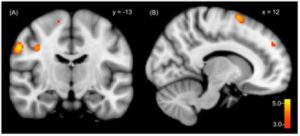

Figure 1: fMRI of DID brain activity

fMRI scans display a significant increase in regional cerebral blood flow in the emotional or traumatic alters’ brains compared to the normal alters brains. The emotional alter displays increased activation of areas that deal with processing sensory information and motor activity while the normal one appears stable [5].

When specifically looking at brain activity, Schlumpf et al. (2013) provided evidence that different alters utilize different regions of the brain [5]. The traumatic or emotional alter had a more active prefrontal cortex and sensory-motor areas of the brain, suggesting that the traumatic alters may rely more on these regions, possibly because of heightened levels of anxiety due to past trauma [5]. On the other hand, the normal alter showed greater activation in the thalamus, which is used for sensory and motor processing, indicating that the different brain areas may impact memory recall in the presence of an alter [5]. Further research similarly displayed that parts of the brain that are used to encode, process, and create memories did not activate in DID patients, overall leading to a lack of memory formation and, therefore, memory gaps and amnesia [2].